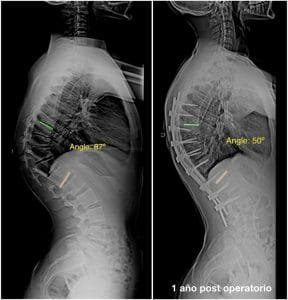

Si hay una cifosis mayor a 70º y con esqueleto maduro se puede recurrir a un tratamiento quirúrgico.

Curvas de más de 90 ° o curvas más pequeñas que no corrigen más del 50% en radiografías de hiperextensión.